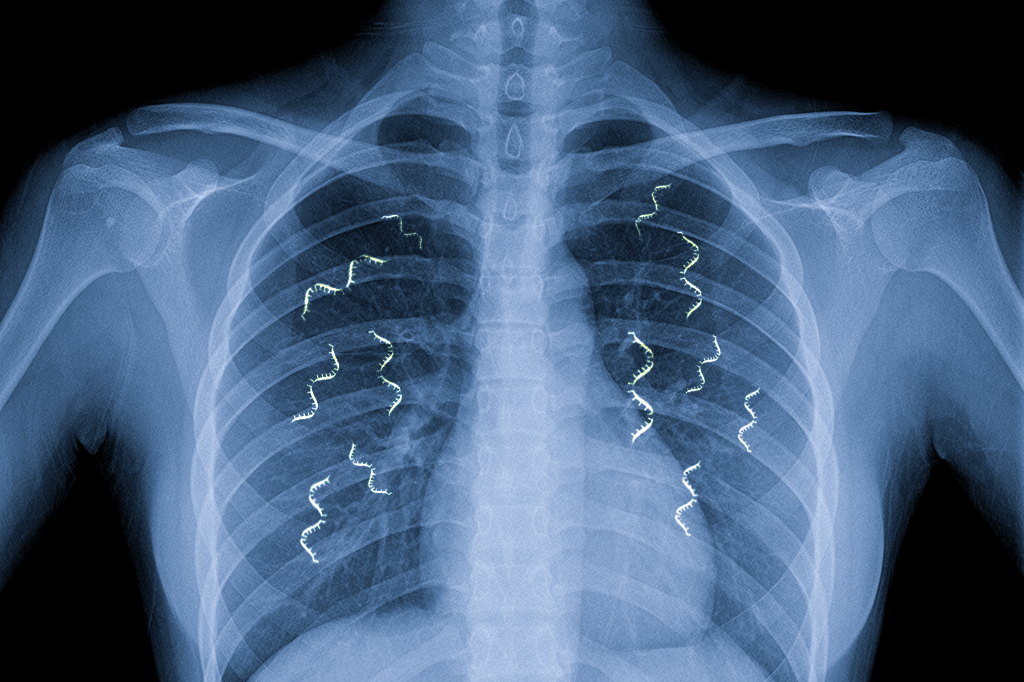

Isso fez um grupo de pesquisadores do MIT pensar: o que aconteceria se você inserisse RNAm com instruções para fabricar medicamentos no corpo de um paciente? Será que os ribossomos leriam essas instruções e passariam a fabricar os medicamentos com a mesma eficiência com que produzem as proteínas originais? A resposta, publicada em um artigo científico na última sexta-feira (4), é sim. E no caso de uma doença pulmonar como a fibrose cística, o RNAm poderia ser ministrado de maneira bem simples: misturado no soro durante seções de inalação.

Os testes foram feitos em camundongos. Os pesquisadores criaram uma molécula de RNAm que contém instruções para produzir uma proteína chamada luciferase – que é bioluminescente (ou seja, que emite luz). Depois, misturaram o RNAm no vapor e fizeram os camundongos respirá-lo. Não deu outra: os pulmões dos camundongos prontamente absorveram o RNAm, e os ribossomos passaram a produzir a proteína luciferase. Em 24 horas, tudo estava aceso feito o abdômen de um vagalume.